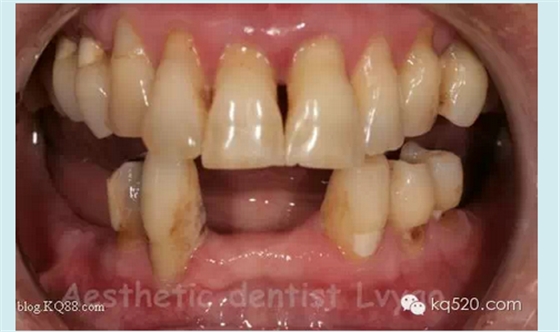

修復(fù)前口內(nèi)影像